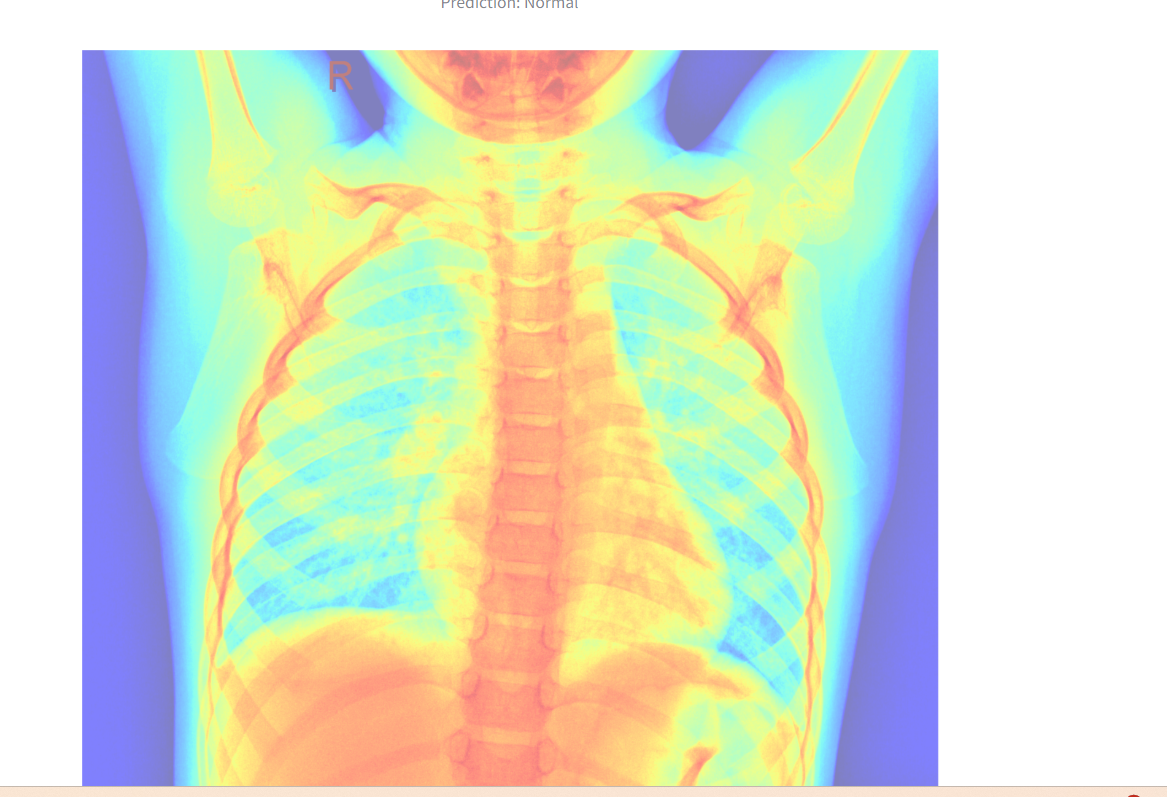

Visualization:

A heatmap overlay is generated for better interpretability.

The heatmap overlay

Visualization: The app enhances interpretability with a heatmap overlay.

Incorporating explainability tools such as Grad-CAM for enhanced interpretability.